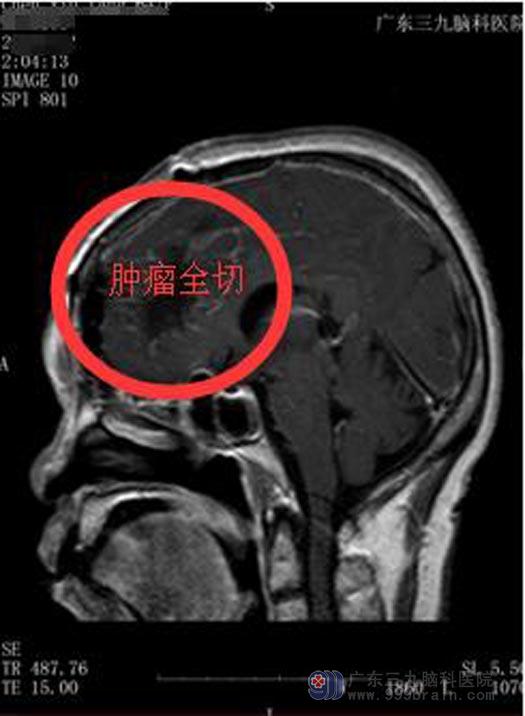

分析肿瘤具体情况、充分术前准备后,由综合神经外科鲁明主任主刀在全麻下行左额部廉旁脑膜瘤切除术,分块将肿瘤全切,术中出血少,正常的脑组织、颅神经和血管得到有效的保护,术毕生命体征平稳。术后陈女士神志清醒,积极地康复治疗,目前已恢复良好出院。